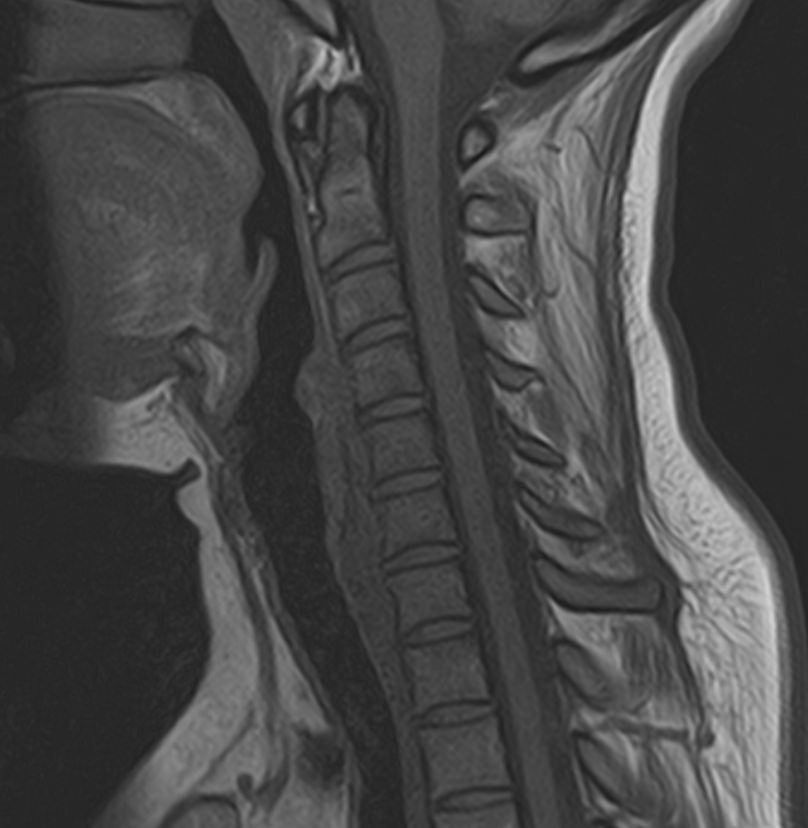

Шейный отдел позвоночника — это самый подвижный сегмент позвоночного столба, который испытывает повышенные нагрузки, подвержен травмам и развитию различных заболеваний. В эту анатомическую область входит 7 верхних позвонков, спинной мозг с отходящими от него нервными корешками, а также проходят крупные сосуды, кровоснабжающие головной мозг.

МРТ шейного отдела позвоночника позволяет проводить диагностику дегенеративных заболеваний позвоночного столба (в том числе межпозвонковых грыж, протрузий, остеохондроза), выявлять воспалительные, травматические изменения и объемные образования в области шейных позвонков и спинного мозга.

В клинике «Доступная медицина» данное исследование проводится на современном высокопольном магнитно-резонансном томографе экспертного класса TOSHIBA VANTAGE TITAN 1,5 Тесла. Напряженность магнитного поля 1,5 Тесла обеспечивает высокую разрешающую способность аппарата, что позволяет выявлять минимальные изменения в тканях и диагностировать заболевания на начальной стадии.

МРТ шейного отдела позвоночника позволяет выявить практически любые изменения в костных и мягких тканях. Исследование характеризуется высокой результативностью при следующих нарушениях:

• остеохондроз шейного отдела позвоночника;

• грыжи межпозвоночных дисков;

• компрессия спинномозговых корешков и спинного мозга;